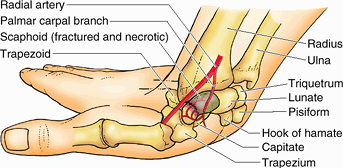

bone. It often results from a fall on the palm when the hand is

the scaphoid (Fig. B6.4). Pain occurs primarily

on the lateral side of the wrist, especially during dorsiflexion and

abduction of the hand. Initial radiographs of the wrist may not reveal

a fracture; often this injury is (mis-)diagnosed as a severely sprained wrist.

Radiographs taken 10–14 days later reveal a fracture because bone

resorption has occurred there. Owing to the poor blood supply to the

proximal part of the scaphoid, union of the fractured parts may take at

least 3 months. Avascular necrosis of the proximal fragment of the scaphoid (pathological death of bone resulting from inadequate blood supply) may occur and produce degenerative joint disease of the wrist. In some cases, it is necessary to fuse the carpals surgically (arthrodesis).

fractured bony parts because of the traction produced by the attached

muscles. Because the ulnar nerve is close to the hook of the hamate,

the nerve may be injured by this fracture, causing decreased grip

strength of the hand. The ulnar artery may also be damaged when the

hamate is fractured.